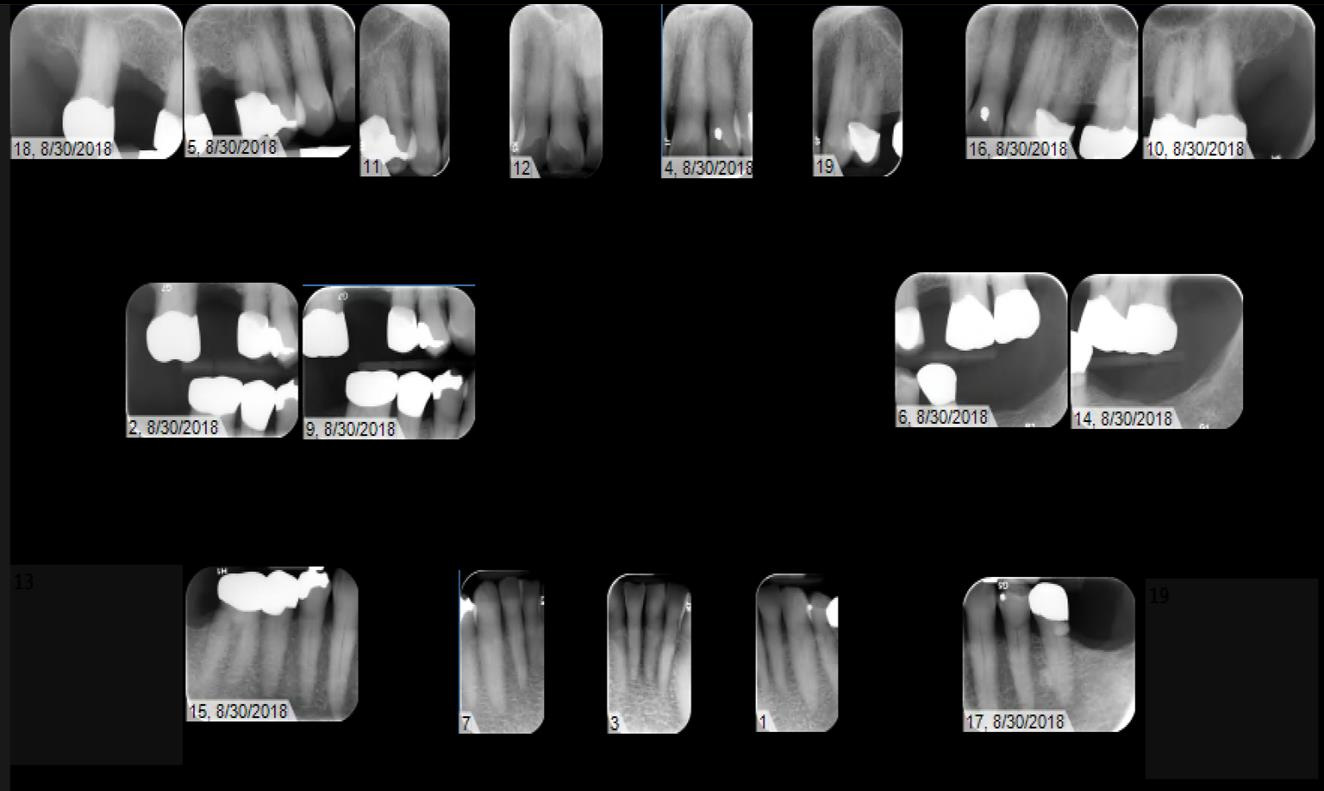

Radiographic evaluation: Full Mouth Series and Panoramic X-ray

- History of Restorative work

- PFM crowns

- #s 4, 12

- Gold crowns

- #s 2, 14, 15, 20, 30

- Zirconia(?) crown

- #29

- Gold inlay

- #28

- Amalgam fillings

- #5 DO, #10 L, #21 O

- Exts

- Mentioned failed RCT leading to extraction